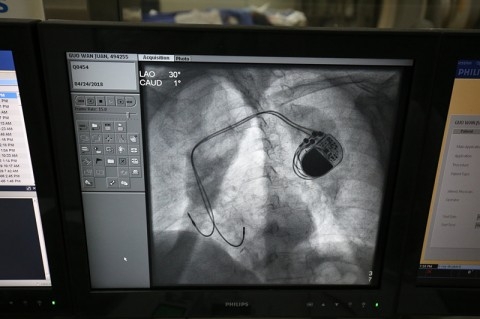

为了让广大人民群众切实享受到国家科技发展带来的实惠,附属金山医院心内科龚辉团队第一时间通过审批,引进这颗中国“心”。通过对患者的充分沟通,4月24日下午,龚辉团队在附属金山医院介入中心进行了这颗中国“心”在金山区的首次植入。

当天的手术进行了大约两个小时,龚辉团队完成了对患者的一台双腔和一台单腔起搏器的植入。龚辉主任表示,国产起搏器的植入很方便,基本和外资品牌没有区别。两位患者植入“中国心”之后,表示体感良好,安全返回病房。作为“心系列”国产起搏器在金山区的首次植入,本次手术非常成功。